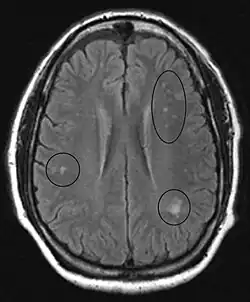

Im Gehirn selbst sind die Veränderungen weniger schwerwiegend. Hier treten kleine, meist subkortikal gelegene Herde mit Nervenfasernverfall und Anhäufung von Astrozyten auf, sowie runde Blutungsherde mit Anlagerung von Gliazellen. Diese pathologischen Veränderungen können auch in der Hinterwurzel des Rückenmarks und, in geringerem Ausmaß, bei peripheren Nerven auftreten. Sie können mittels Magnetresonanztomographie erkannt werden.[27]